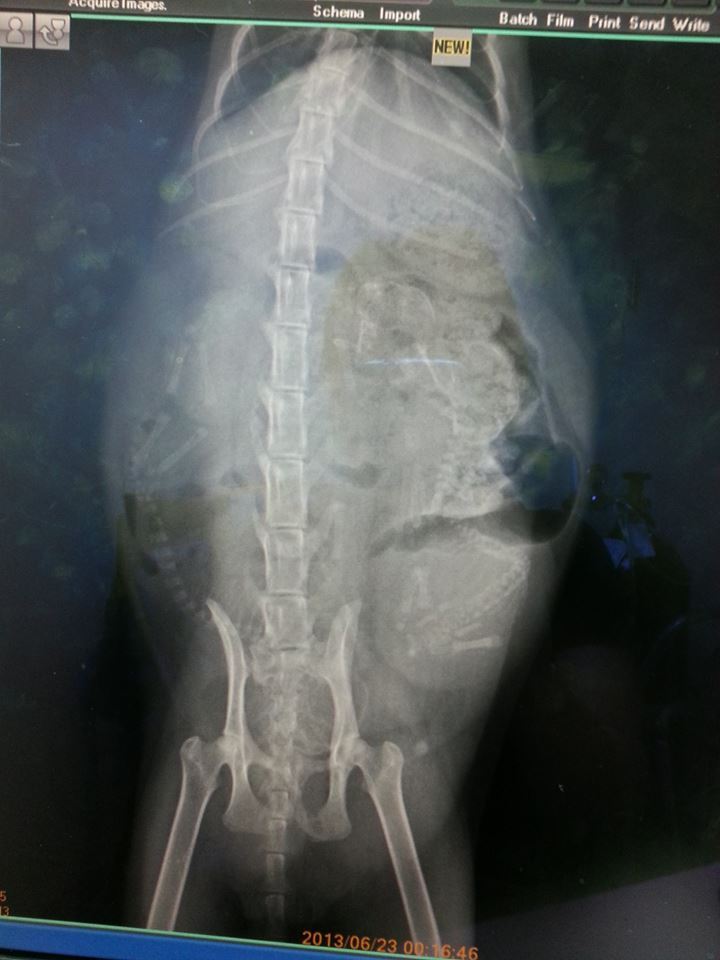

在這期間,因為貓咪肚子太大,每天都是癱坐,還帶她照一次超音波,進行產檢。(其實是確定是否懷孕,原本擔心是腹水……)然後醫生依照X光,告知有5隻小貓,且貓頭已轉向快生了……

貓媽媽真的超乖!此時的她應該很不舒服、全身癱軟無力……但仍配合全程檢查。照X光發現,有兩條小脊髓很明顯,貓媽媽肚子內還有兩隻小貓!決定緊急進行手術。

開刀後發現其實有3隻,連生出的4隻,共懷7隻,難怪生到後面都沒力了!再加上母貓營養不夠,其中一隻發育不良,在肚中就已死亡。